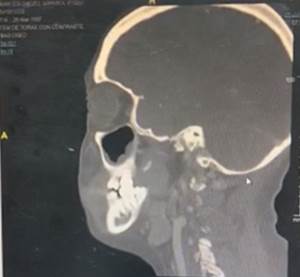

Among the auxiliary examinations of highlighted images presented, thickening of the mucosa in ethmoid cells, a radiolucent image in the upper palate (Figura 2), slight adenopathy at the retromandibular level (Figura 3), thickening of the mucosa of both maxillary sinuses, and thickening of the middle turbinate, there is a slight deviation to the left of the nasal septum (Figura 4), in the axial tomography of the head-lower part, a radiopaque image is appreciated in the left area of the palate, consistent with the necrosis evidenced in the physical examination , there is evidence of the presence of contrast hyper-uptake nodules and the presence of small adenopathies (Figura 5).

Figure 2. Sagittal head tomography with contrast showing thickening in the mucosa of the ethmoid cells, lucid radio image in the upper palate corresponding to the necrotic area described in the physical examination, no lymphadenopathy is appreciated.